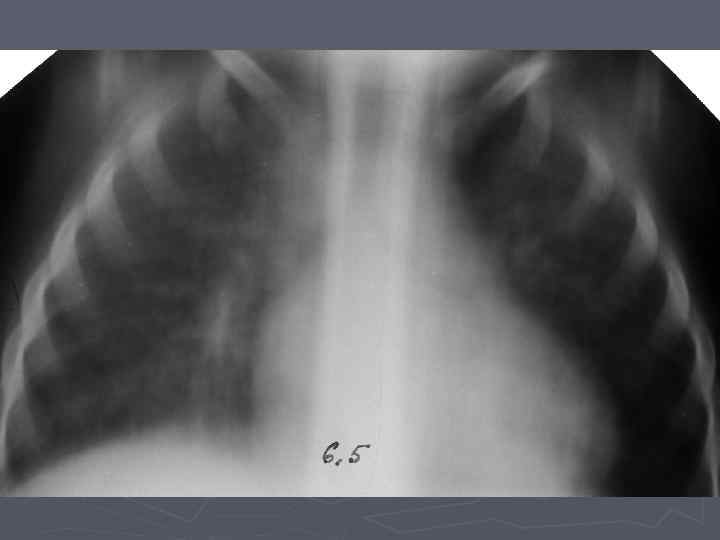

Клинические особенности туберкулеза у взрослых на фоне ВИЧ-инфекции ► ► ► ► ► Внутригрудные аденопатии; Милиарные высыпания; Частое поражение базальных сегментов легких; Относительно редкое поражение каудоапикальных сегментов легких; Распад легочной ткани диагностируется в 2 раза реже; Нередок плевральный выпот; Велика склонность к генерализации туберкулезной инфекции с множественными внелегочными локализациями. Присоеднинение туберкулезного менингита; МБТ в мокроте выявляются одинаково часто у ВИЧ негативных и позитивных лиц, по крови МБТ методом посева выделяются у 70% пациентов; При отсутствии признаков локального туберкулеза и неясной лихорадке – посев костного мозга часто дает МБТ+.

Клинико-эпидемиологические особенности туберкулезной инфекции у ВИЧинфицированных и больных СПИДом детей ► Вертикальный путь заражения ВИЧ; ► Ранний возраст; ► Семейные контакты с болеющими туберкулезом в активных фазах; ► Отсутствие вакцинации БЦЖ; ► Выраженный локальный процесс, протекающий с: § бронхолегочными поражениями; § Распадом легочной ткани; § Обсеменением легочной ткани.

Неблагоприятное сочетание ряда обстоятельств: § Ранний возраст; § Тяжелые семейные контакты; § Отсутствие вакцинации - и у свободных от ВИЧ-инфекции детей всегда приводят к развитию локального туберкулеза, протекающего, как правило, ОСЛОЖНЕННО с бронхолегочными поражениями, распадом легочной ткани, диссеминациями.